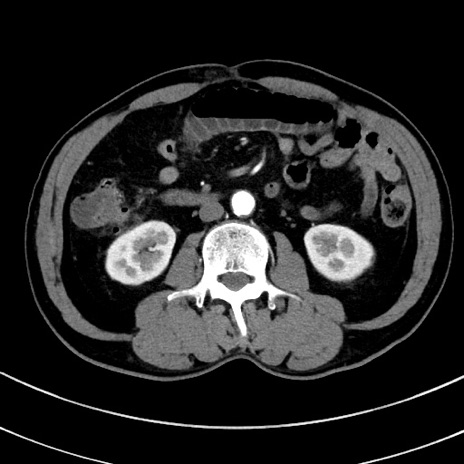

症例8(横断像)

【症例】 60歳代男性

【主訴】 黒色吐物

【現病歴】 4日前から嘔気自覚、2日前の朝食後にも嘔気あり、自分で手で嘔吐反射起こし嘔吐したところ血が混ざっていたため受診。

【既往歴】 5年前汎発性腹膜炎を伴う急性虫垂炎で手術、高血圧、前立腺肥大症、高脂血症

【身体所見】 腹部正中に手術癩痕あり 腹部平坦・軟圧痛なし膨満感あり

【データ】WBC 8400、CRP 4.54